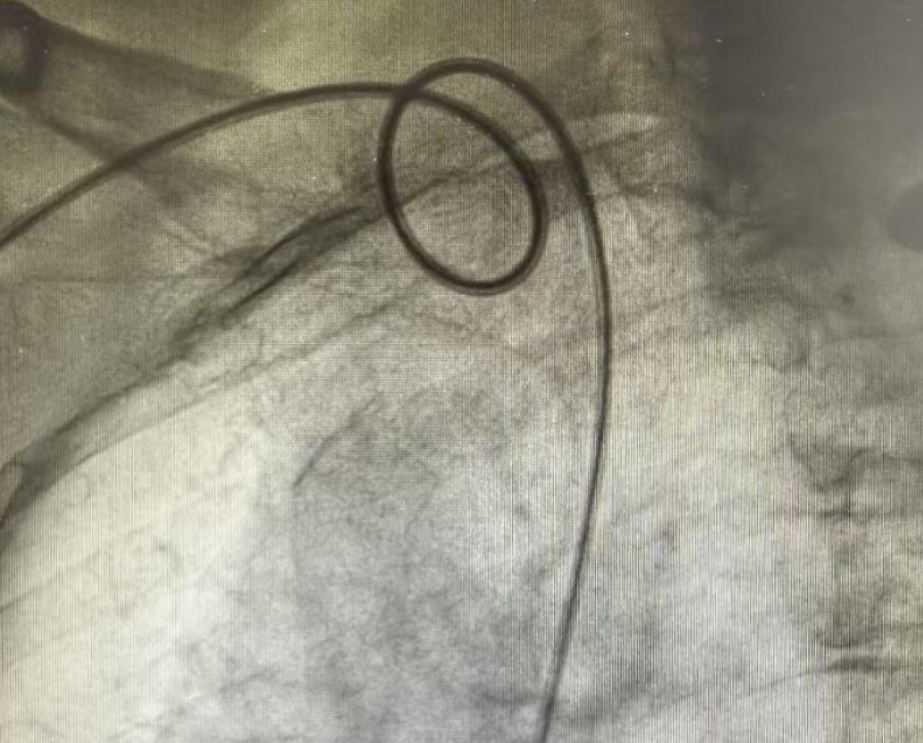

明确诊断是治疗的第一步,而冠状动脉造影是诊断冠心病的“金标准”。然而,当心脏康复科主任吴志刚带领团队为张阿姨实施造影时,却遇到了一个巨大的技术挑战:患者锁骨下动脉严重迂曲——这条血管是导管到达心脏冠状动脉的必经之路,其极度迂曲的形态如同盘绕的“迷宫”:

导管在如此扭曲的血管中穿行异常艰难,操作稍有不慎可能导致导管无法前进、打折,甚至损伤血管内膜。

严重迂曲大大增加了将导管精准送达冠状动脉开口的难度,直接影响造影图像质量和后续评估的准确性,这对术者的经验、操作技巧和耐心都是严峻考验。

面对这个“拦路虎”,吴志刚和团队凭借丰富的经验和精湛稳定的操作技术,在毫米级的方寸之地精准操控导丝,巧妙地运用导管塑形、轻柔旋转推送等技巧,最终成功穿越这段险峻的“血管迷宫”,将导管稳稳送达目标位置,完成了高质量的冠状动脉造影检查。